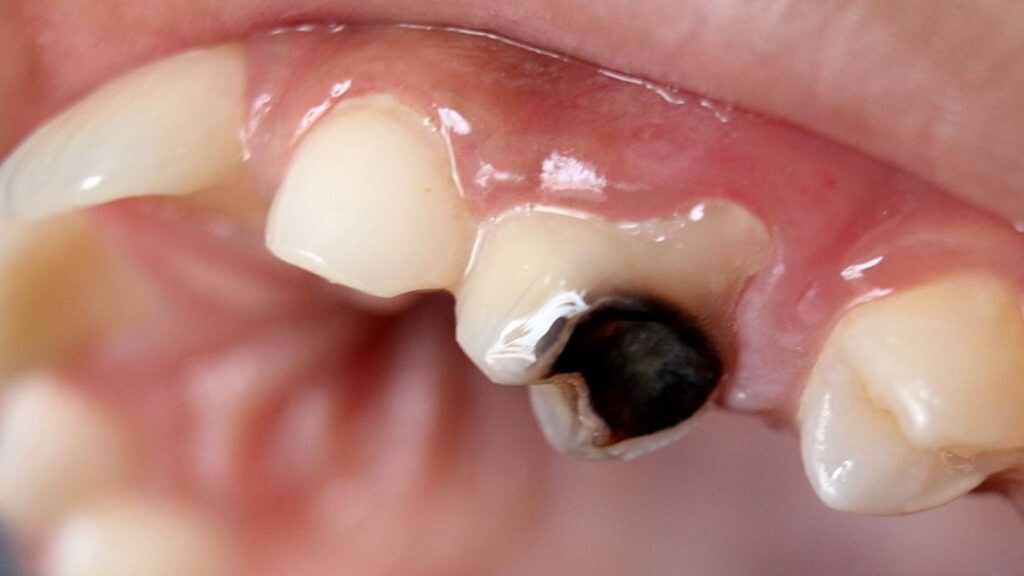

Enamel Damage can result in black teeth

Decay or cavities are the most common reason for teeth turning black. When the pulp becomes infected, the black color begins inside the tooth and works its way to the surface. The black appearance often starts as a few dark spots, but when left untreated, the whole tooth can turn black. Turning black is usually a gradual transformation that begins with brown or gray spots or small dots of black near the gum line.

An injury to the mouth can damage the tooth so badly that it dies, in which case the tooth may also turn black.